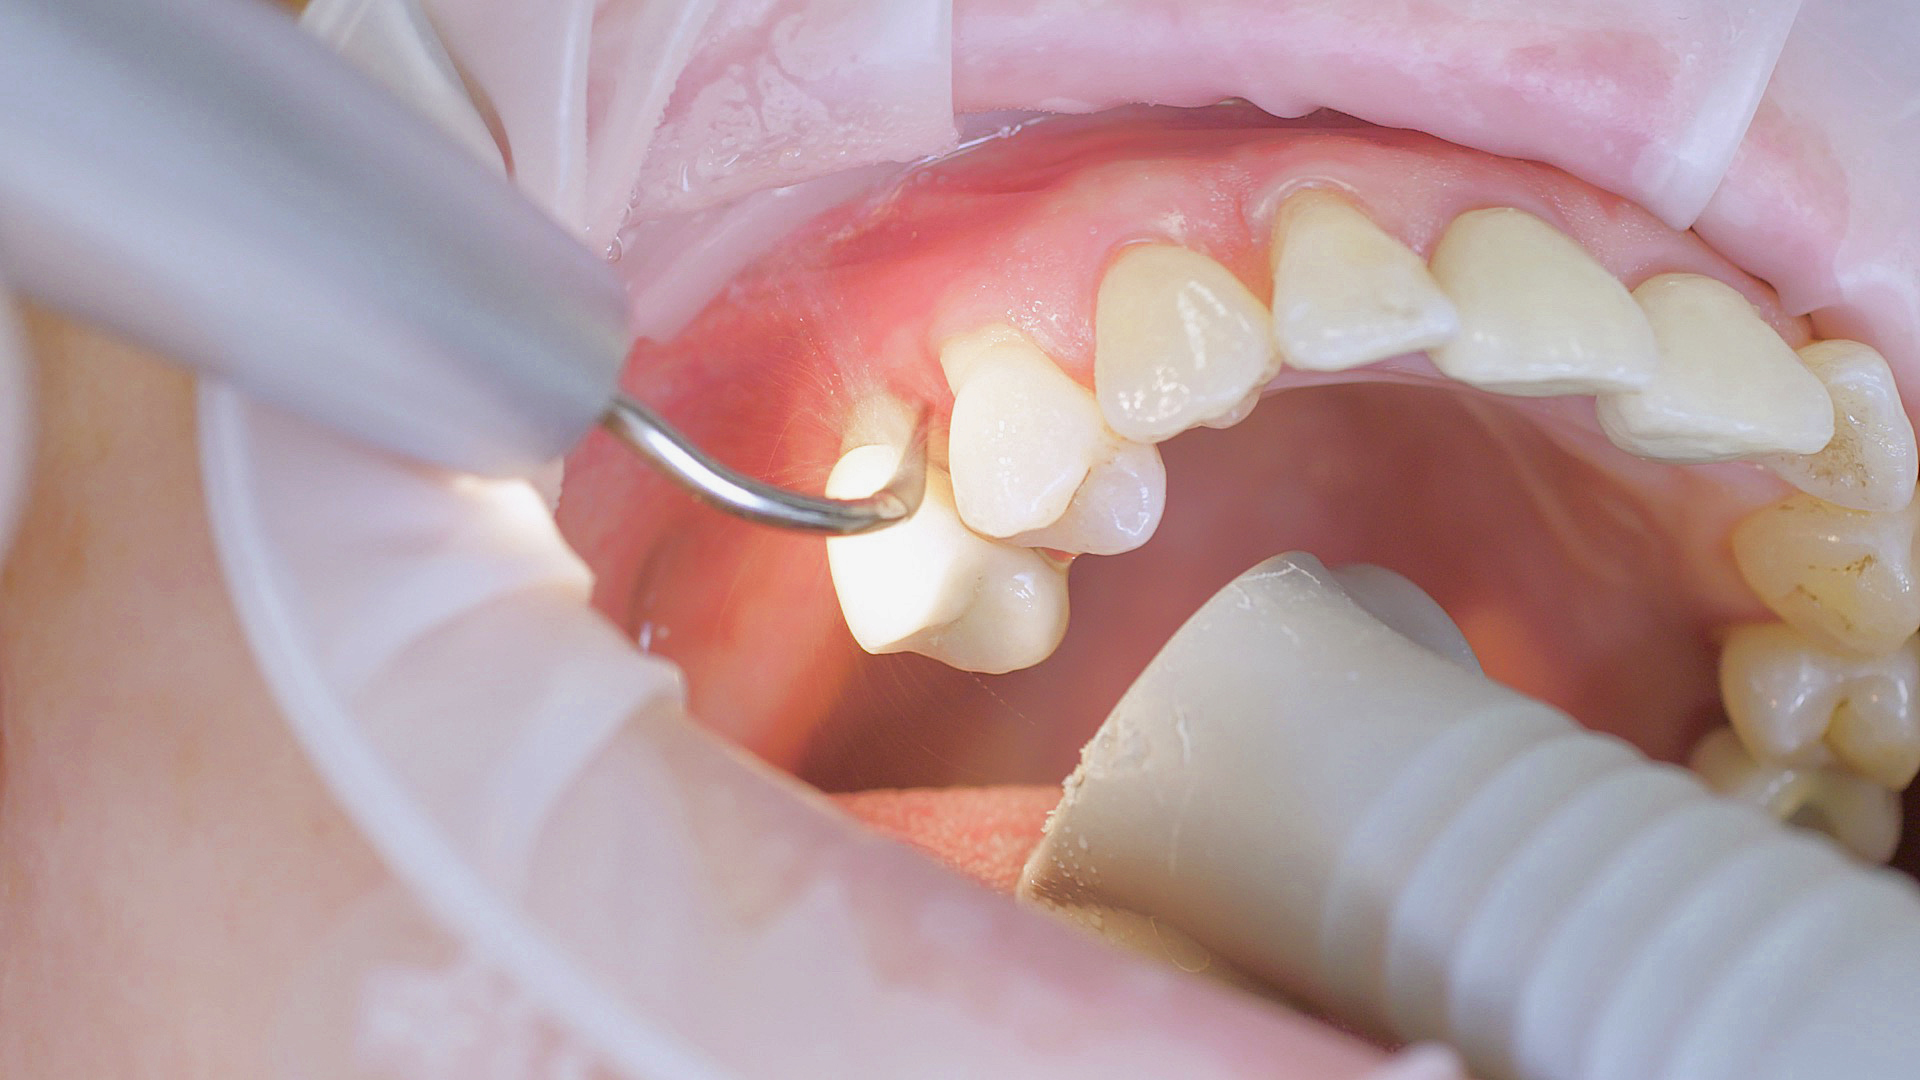

Every dental examination is based on a detailed medical history combined with targeted diagnostics con- taining as much detail as possible: The dentist records systemic risk factors such as diabetes or smoking and identifies any potential increased tendency to inflammation.[3] Hard and soft tissues are examined and periodontal pockets are probed in a screening test according to PSR (Periodontal Screening and Recording). In case of abnormal findings, the periodontal status is then re- corded and therapy is initiated where necessary. This treatment begins with professional biofilm management, by using, for example, rotary cups and polishing com pounds (Fig. 1), and comprehensive instructions in oral hygiene. Sonic or ultrasonic systems remain an effective alternative or supplement to manual instruments for sub- gingival debridement and biofilm management (presentation by Prof. Dr Ulrich Schlagenhauf; Fig. 2). Supplementary use of photodynamic therapy, air polishing or local and systemic antibiotics is not adequately documented (Prof. Dr Sema Hakki).[4] According to Dr Sergio Bizzarro, improved biomarker diagnostics may lead to an increase in customised patient therapy in the future.